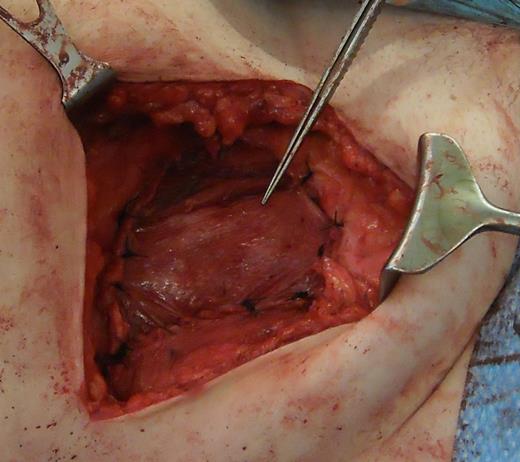

A 43-year-old Caucasian female presented to her General Practitioner in April 2012 with a 2-year history of a firm, painful swelling in the right flank. MRI revealed a 5.0 × 6.0 × 7.0 cm enhancing lesion with areas of necrosis, which was invading the antero-lateral abdominal wall (Fig. 1 ). With radiological features highly suggestive of a sarcoma, she underwent an ultrasound-guided biopsy, which classified the mass as a borderline myoepithelial tumour. The patient underwent an uncomplicated resection of the mass, which left a 10 × 10 cm right-sided antero-lateral abdominal wall defect. The defect was repaired using a Biodesign® biological graft. Initially, a layer of the biological mesh was used to cover the intact peritoneum with attachments cranially to the ribs and inferiorly to the right iliac crest. The external oblique was mobilized to partially cover the mesh, and a further layer of the biological mesh attached over it with Ethilon™ (Fig. 2). The patient had an uncomplicated postoperative recovery. The tumour histology revealed a 6.5 × 6.0 × 5.5 cm myxoid mass; immunohistochemistry analysis favoured a benign/borderline myofibroblastic tumour. At 24-month follow-up, she had good wound healing with a small area of paraesthesia inferior to the scar. An MRI showed good graft incorporation and no evidence of disease recurrence or hernia (Fig. 3).

Depicting the porcine intestinal biological mesh in place after tumour excision.